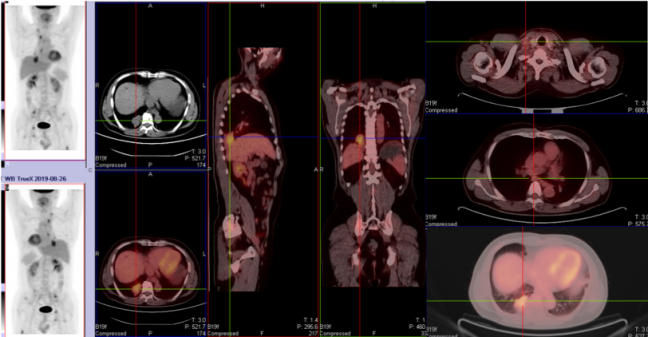

骨骼是肺癌常见的转移部位之一,骨转移癌会导致骨痛、病理性骨折、脊髓压迫、高钙血症等骨相关事件(SRE),其中,骨痛是骨转移癌最常见的临床症状,严重影响患者生活质量。地舒单抗,首个落户中国的核因子κB受体活化因子配体(RANKL)抑制剂,为防治SRE提供新的选择。本次分享地舒单抗治疗以骨痛为主要症状的EGFR突变晚期肺癌骨转移患者案例,希望为SRE的防治带来启迪与思考。 白引苗 空军军医大学第一附属医院肿瘤科 主治医师 中国抗癌协会肿瘤标志物专业委员会 委员 陕西省抗癌协会肿瘤化疗专业委员会 委员 陕西省抗癌协会肿瘤热疗专业委员会 委员 陕西省抗癌协会多原发和不明原发肿瘤专业委员会委员 擅长食管癌、胃癌、结直肠癌、胰腺癌等消化系统、肺癌及妇科常见恶性肿瘤的化疗、靶向治疗及免疫治疗等内科治疗。参译著作1部,参编著作1部,发表核心期刊论文多篇。 一般资料:患者男性,60岁 主诉:右侧肩部疼痛 现病史:2019年8月因右侧肩部疼痛于外院就诊,疼痛NRS评分3-4分,口服依托考昔症状可缓解 个人史:否认吸烟、饮酒嗜好 家族史:1兄因“胃癌”病故 辅助检查: 外院右肱骨MRI:右侧肱骨骨转移可能,合并肱骨中段骨质破坏。 外院胸部CT(图1):右肺下叶周围型肺癌,可疑肺门、纵隔淋巴结转移,T3/4/8椎体骨转移。 图1 胸部CT(箭头指示右肺下叶病变) PET/CT(18F-FDG)(图2-3):右肺下叶基底段软组织病变(3.7 cm×4.6 cm×4.7 cm,SUV max 6.9,平均值6),浅分叶、边缘见毛刺;右侧锁骨上下区、隆突区稍大淋巴结(长径0.6 cm-1.4 cm,SUV max 2.5-4.6,平均值2.2-3.2),考虑转移;脊柱多个椎体及附件、双侧多个肋骨、骨盆多处、双侧股骨上段多发骨质破坏(SUV max 2.0-5.7,平均值1.7-3.9),考虑转移。 图2 PET/CT提示右肺下叶基底段病变及右锁骨上下区、隆突区稍大淋巴结 图3 PET/CT提示多发骨质破坏 患者接受CT引导下经皮右肺病变穿刺活检,病理(图4):光镜见异型细胞呈条索状、腺管样排列,细胞核大、深染,异型性明显;免疫组化:AE1/AE3(+),CK5/6(-),CK7(+),CK8/18(+),P40(-),P63(-), Napsin A(+),ALK(D5F3 Ventana IHC)(-),TTF-1(+),Ki67 30%,支持腺癌。 肿瘤标志物:CYFRA21-1 5.8 ng/ml(参考值:0-3.3 ng/ml),CEA、SCC、NSE正常。 基因检测:EGFR基因19del突变。KRAS、NRAS、PIK3CA、BRAF、HER-2基因未检测到突变;ALK、ROS1、RET基因未检测到融合。 诊断:肺恶性肿瘤(右侧,腺癌,cT2N3M1,IV期,EGFR 19del);骨继发恶性肿瘤(多发);淋巴结继发恶性肿瘤(多发)。 双管齐下、并驾齐驱——抗癌治疗与唑来膦酸齐头并进 2019年9月患者接受奥希替尼80 mg/日一线治疗,同时接受唑来膦酸4 mg/月改善SRE。1个月后复查CT示右肺病变缩小40%(4.7 cm至2.8 cm);肿瘤标志物CYFRA21-1由5.8 ng/ml降至3.67 ng/ml;右肩部疼痛消失(停用止痛药)。 2020年3月复查胸部CT(图5)提示:肺部病变进展(增大39.3%,2.8 cm至3.9 cm);肿瘤标志物CYFRA21-1缓慢升高至7.05 ng/ml。考虑局部进展,在奥希替尼基础上联合培美曲塞+卡铂治疗4个周期,后给予奥希替尼联合培美曲塞维持治疗14个周期。 图5 胸部CT(2020年3月,箭头指示右肺病变) 最佳疗效:右肺病变缩小51.3%(至1.9 cm)(图6);肿瘤标志物CYFRA21-1由7.05 ng/ml降至1.4 ng/ml。 图6 二线治疗前(左图)后(右图)胸部CT比较(箭头指示右肺病变) 2021年4月患者感背部钝痛,NRS评分5-6分,口服氨酚羟考酮330 mg/8 h,症状可缓解。骨扫描(ECT)与单光子发射计算机断层扫描(SPECT)/CT提示骨转移加重。停用唑来膦酸,使用地舒单抗120 mg/月,疼痛有缓解。 2021年9月复查胸部CT示右肺下叶病变进展(1.9 cm至3.4 cm)。肿瘤标志物CYFRA21-1由10.73 ng/ml升至13 ng/ml。患者感背部疼痛加重,NRS 评分5-6分。行CT引导下右肺病变再次穿刺活检,病理提示肺腺癌,PD-L1(SP263)(TPS=80%),Ki67 85%。基因检测:EGFR 19del,KRAS、NRAS、PIK3CA、BRAF、HER-2基因及MET exon14无突变;ALK、ROS1、RET基因无融合。 遂调整为白蛋白结合型紫杉醇化疗2周期,奥希替尼和地舒单抗方案同前,患者背部疼痛消失。 2021年11月复查PET/CT:原右肺下叶基底段团块状软组织病变较初诊缩小(1.8 cm×1.6 cm×3.8 cm);原右侧锁骨区多发淋巴结消失;原隆突区稍大淋巴结缩小(0.5 cm);原脊柱多个椎体及附件、双侧多个肋骨、骨盆多处、双侧股骨上段多发骨质破坏,病变密度增高,考虑治疗有效,部分仍有代谢活跃;右侧颞叶片状低密度影。查头颅MRI(图7):左侧额叶大脑镰旁(0.7 cm×0.7 cm×1 cm)、右侧颞叶脑皮质表面(1.2 cm×1.3 cm×0.8 cm)异常强化灶,考虑转移。 图7 头颅MRI(箭头指示颅内病变) 经MDT讨论,建议脑部病变随诊观察。鉴于出现脑转移癌,调整为伏美替尼80 mg/日口服、白蛋白结合型紫杉醇静脉化疗;继续予地舒单抗。 患者治疗期间碱性磷酸酶(ALP)水平变化如图8所示。 图8 血清碱性磷酸酶变化情况 患者于2019年8月因右侧肩部疼痛就诊,确诊右肺腺癌Ⅳ期伴多发骨转移及淋巴结转移,EGFR 19del突变。一线治疗:奥希替尼(80 mg/日)+骨改良药物唑来膦酸(4 mg/月),最佳疗效:右肺肿瘤PR(缩小40%)、疼痛症状缓解,一线治疗PFS时间7个月。2020年3月,肺部病灶进展,予奥希替尼+培美曲塞联合卡铂4周期,后培美曲塞维持治疗14周期,继续予唑来膦酸治疗;2021年4月背部钝痛加重,骨扫描提示骨病变进展,遂停用唑来膦酸,予地舒单抗120 mg/月治疗至2021年9月,二线PFS 18个月。后因肺部病灶进展,三线治疗给予奥希替尼+白蛋白结合型紫杉醇及地舒单抗,患者背部疼痛症状消失。2021年11月头颅MRI示颅内转移,调整为予伏美替尼(80 mg/日)联合白蛋白结合型紫杉醇及地舒单抗治疗。 张红梅 西京医院肿瘤科主任 肿瘤学博士,硕士研究生导师 中国抗癌协会CMUP 副主委 中国临床肿瘤学会免疫专家委员会 常委 陕西省医学会肿瘤内科分会 副主委 主要从事肺癌等恶性肿瘤的内科治疗 我国肺癌发病率和死亡率均位于恶性肿瘤首位,20%-30%的晚期肺癌会发生骨转移[1],45%的肺癌骨转移患者会出现相关临床症状[2]。肺癌骨转移是患者生活质量降低、生存期缩短的独立危险因素,SRE如骨痛、病理性骨折、脊髓压迫等,不仅给患者带来生理上的痛苦与不便,也引发患者心理打击。因此,对于晚期肺癌骨转移患者,在控制原发疾病同时,亟需积极防治SRE,以达到提高患者生活质量、缓解生理心理痛苦、延长生存期的目的[3]。 本例肺癌同时性骨转移案例,以骨痛为首发症状,在奥希替尼治疗肺癌同时,首先予以唑来膦酸防治SRE,治疗初期患者症状一度改善。但随着疾病进展,唑来膦酸应用近20月后患者再次骨痛加重,影像学提示骨损害加重,对于这种骨病变进展、骨痛加重的临床问题,如何制定进一步治疗方案? 地舒单抗是IgG2型单克隆抗体,通过与RANKL结合,阻止其激活破骨细胞、破骨细胞前体和破骨细胞样巨细胞表面的核因子-κB受体活化因子(RANK),从而达到抑制肿瘤生长、减少骨破坏的目的。早在2010年,地舒单抗获得美国食品药品监督管理局(FDA)批准用于治疗实体瘤骨转移,目前已积累了丰富的证据临床研究和真实世界数据,显示其有效性和安全性。 地舒单抗与唑来膦酸治疗实体瘤骨转移和多发性骨髓瘤的Ⅲ期临床研究显示,地舒单抗可延缓首次出现SRE的时间(21.4个月 VS. 15.4个月)[4]。其中非小细胞肺癌患者,地舒单抗组较唑来膦酸组中位生存期(OS)延长1.5个月(9.5个月 VS. 8.0个月)[5]。安全性方面,地舒单抗也具有一定的优越性:与唑来膦酸组比较,地舒单抗组贫血、厌食症、肾脏不良事件、新发原发性恶性肿瘤的发生率较低[6]。地舒单抗通过网状内皮系统清除,不增加肾脏负担,对于肾功能不全的患者可作为首选。此外,作为皮下注射制剂,28天用药一次,无需住院完成,无疑为口服靶向药的肺癌骨转移患者带来极大的便利。 本例患者经唑来膦酸治疗后再次出现SRE,改用地舒单抗治疗至今,患者骨痛症状缓解,随访血清ALP水平逐渐下降,且耐受性良好。对这位长期与肺癌抗争的晚期患者,地舒单抗减轻了身体的疼痛,带来心灵的慰藉,实现临床获益。 2020年11月20日,地舒单抗在中国获得国家药品监督管理局(NMPA)批准,用于预防实体瘤骨转移及多发性骨髓瘤引起的SRE,随着药物可及性的进一步提高,期待地舒单抗可造福更多饱受骨转移折磨的中国肿瘤患者。 参考文献 1、Her nandez R K , Wade S W, Ly man GH, et al. I ncidence of bone metastases in patients with solid tumors: analysis of oncology electronic medical records in the United States. BMC Cancer, 2018, 18(1): 44. 2、Tsuya A, Kurata T, Tamura K, et al. Skeletal metastases in non-small cell lung cancer: a retrospective study. Lung Cancer, 2007, 57(2): 229-232. 3、北京医学奖励基金会肺癌青年专家委员会,中国胸外科肺癌联盟. 肺癌骨转移诊疗专家共识(2019版)[J]. 中国肺癌杂志, 2019, 22(4): 187-207. 4、Henry D, Vadhan-Raj S, Hirsh V, et al. Delaying skeletal-related events in a randomized phase 3 study of Denosumab versus zoledronic acid in patients with advanced cancer: an analysis of data from patients with solid tumors. Support Care Cancer. 2014 Mar; 22(3): 679-687. 5、Scagliotti GV, Hirsh V, Siena S, et al. Overall survival improvement in patients with lung cancer and bone metastases treated with Denosumab versus zoledronic acid: subgroup analysis from a randomized phase 3 study. J Thorac Oncol. 2012 Dec; 7(12): 1823-1829. 6、Fengxia Chen, Feifei Pu. Safety of Denosumab Versus Zoledronic Acid in Patients with Bone Metastases: A Meta-Analysis of Randomized Controlled Trials. Oncol Res Treat. 2016;39(7-8):453-459.基本情况